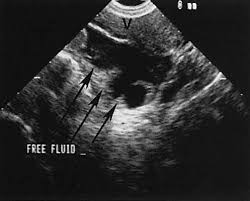

Focused abdominal sonography for trauma revealed trace free fluid (FF) in the pelvic cul-de-sac. No evidence of injury by computed tomography and clinical course. Trace FF (arrow) in pelvis and urinary Obstetrics and Gynecology